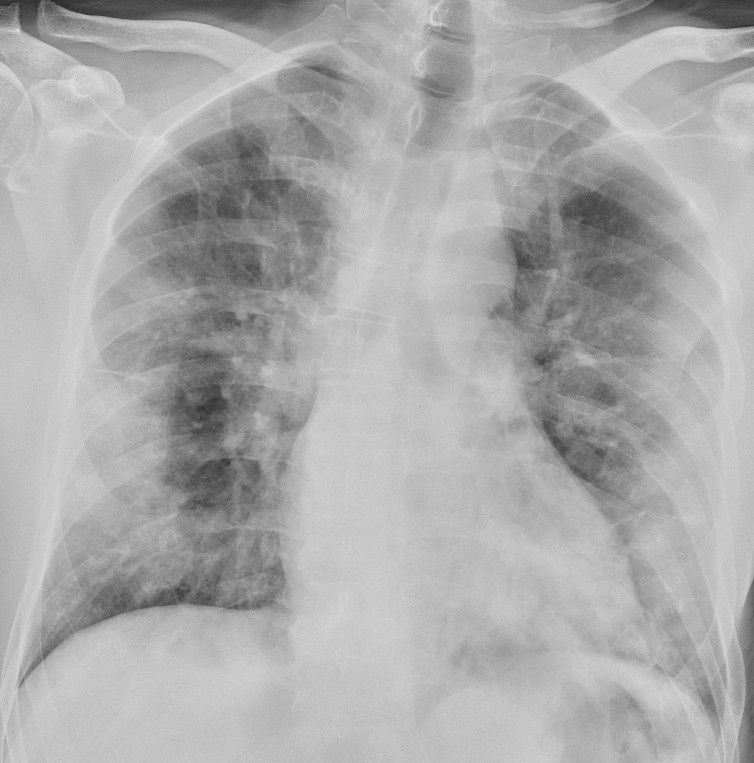

In a dataset from Hong Kong, 69 % had findings on chest X-rays prior to treatment (baseline), but 9 % had findings on chest X-ray prior to positive PCR (14). Sensitivity for chest X-ray was 69 % and for PCR 91 %. The most common X-ray findings were bilateral consolidation and ground-glass opacities with peripheral and caudal distribution. The findings were most pronounced 10–12 days after the onset of symptoms. Figures 1 and 2 show typical chest X-ray patterns in patients with COVID-19.

Patients with moderate symptoms should be evaluated for imaging in accordance with routines for other respiratory diseases. However, chest X-ray is not recommended as the primary modality for specific diagnosis of COVID-19 because a normal X-ray image does not rule out the disease and because typical findings are not specific enough to confirm it either. A chest X-ray may nonetheless be indicated with differential diagnosis in mind.

For inpatients, a bedside X-ray image at an early stage of the disease may be useful as a basis of comparison for interpreting later images. In patients with severe disease, bedside X-rays will be indicated to check technical medical equipment (Figure 3), but daily, routine chest X-rays are not indicated for stable patients. In the course of the disease, bedside X-ray will be indicated on suspicion of complications and for following up and monitoring the progression of the disease.

Typical CT findings vary with symptom duration and can be divided into three stages: an early phase, an intermediate phase that extends from 3–5 days after symptom onset, and a late phase.

There are not always CT findings the first few days after symptom onset. In a material with symptomatic, but unspecified patients, 56 % had normal CT findings within two days of symptom onset (12), declining to 9 % 3–5 days after symptom onset and 4 % 6–12 days after symptom onset. The frequency of findings varies with the severity of the disease. Initial diagnostic imaging yielded normal findings for 18 % in a cohort of patients who were not severely ill, but in only 3 % of patients who were (15). Typical CT findings are multiple, bilateral ground-glass opacities with peripheral distribution, most frequently located in the lower lobes. In the intermediate phase there are increasing amounts of consolidation and affection of several lobes, and increased septation with crazy paving as sign of interstitial affection. In the late phase there is increasing total extension, but ground-glass opacities and consolidation are still the dominant findings (12, 16). Figures 4, 5 and 6 show typical CT findings in different phases of COVID-19.